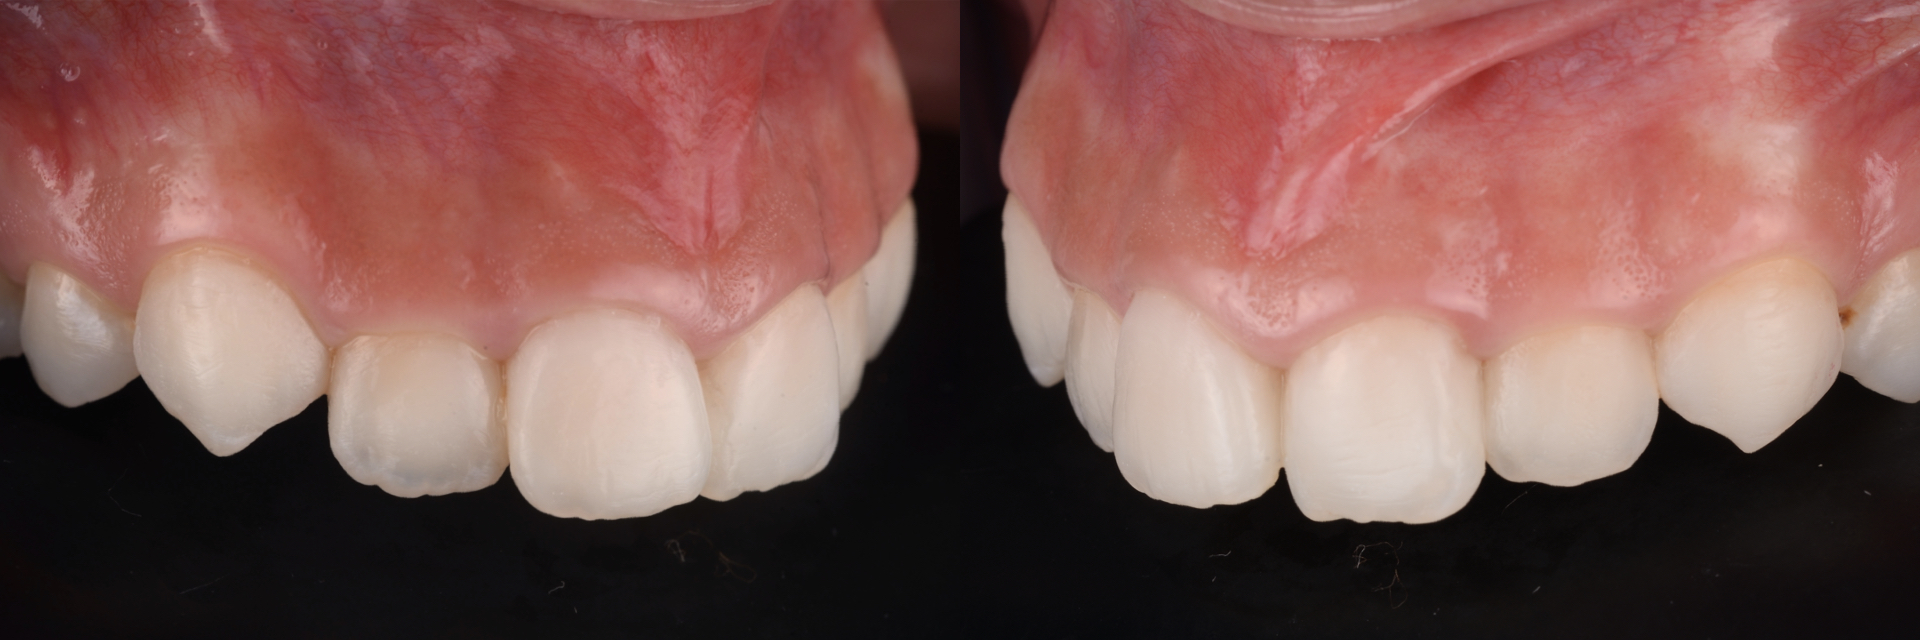

上唇の腫脹を認め、CT検査にて根尖部に嚢胞様透過像を認めた。左上の前歯が不自然に大きく噛み合わせが強くなっていたことがフレアアップの一因と考える。精密根管治療を行い、感染経路を遮断したのち歯根端切除術にて嚢胞を摘出した。

治療前

治療後

歯の保存、嚢胞の摘出、審美的改善